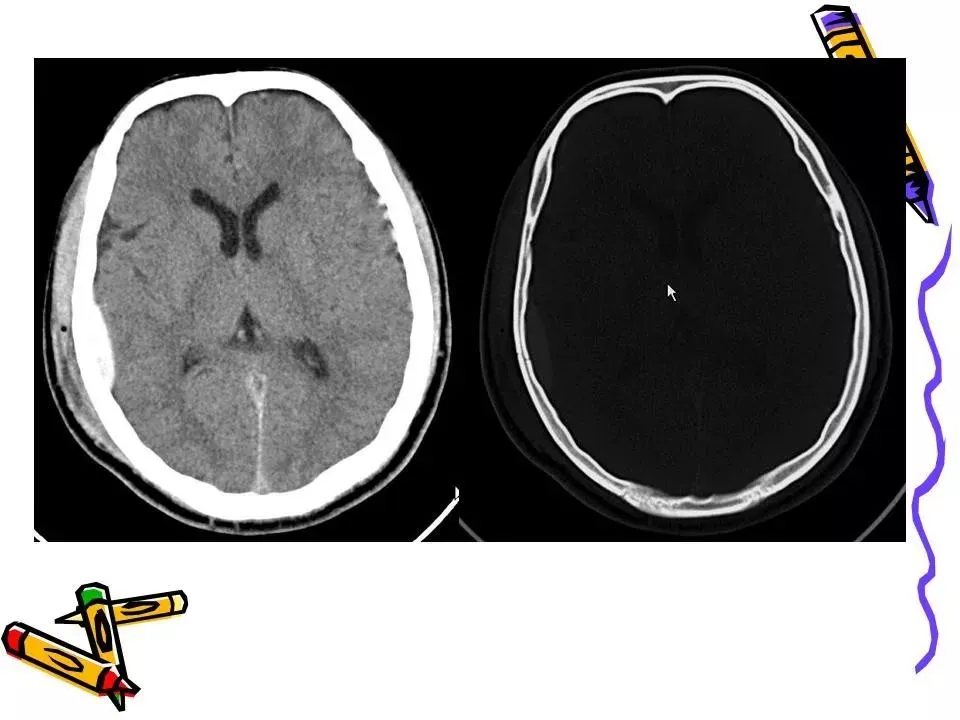

>常见颅脑外伤CT诊断(PPT)

常见颅脑外伤CT诊断(PPT)